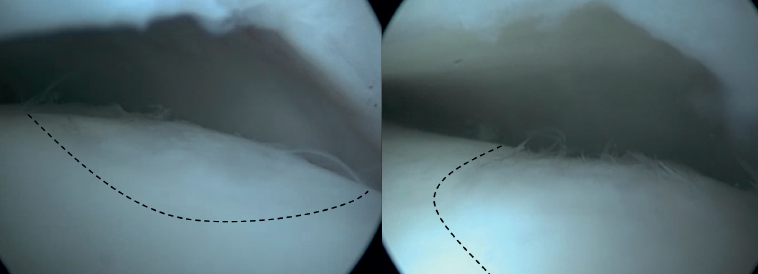

Cartilage implantation techniques, such as autologous chondrocyte implantation (ACI) and matrix-induced autologous chondrocyte implantation (MACI), aim to regenerate the hyaline-like cartilage by implanting harvested and cultured chondrocytes in the osteochondral lesion(46,47,48). These techniques typically use a two-step technique. During the first step, chondrocytes are harvested from a non-weightbearing area of the talus or margins of the lesion during an arthroscopic procedure. Thereafter, these chondrocytes are cultured in-vitro. The second phase consists of reimplanting the cultured chondrocytes in the excised lesion.

For ACI, the cultivated chondrocytes are implanted in a second procedure that occurs typically 3 weeks after step 1(47). During this second procedure, a medial or lateral osteotomy is performed to gain access to the lesion, whereafter the lesion is debrided to prepare for implantation. After implantation, the implanted chondrocytes are then covered by a periosteal flap from the distal tibia(49). Fibrin glue is used to seal the junction of the flap with the articular cartilage(49).

For the MACI-technique, the chondrocytes are cultured and embedded in a biodegradable scaffold, to prevent morbidity of the periosteal flap and harvest-site(46,48). The second step is typically performed 8-12 weeks after harvesting the chondrocytes. Access is gained through medial or lateral osteotomy, and after debridement of the lesion, lesion size is measured using a foil template. The MACI graft is then cut around the template and is placed into the lesion with the side containing the cells facing the defect. Thereafter, fibrin glue is used to secure the graft(50).

These techniques have shown promising results in the knee, resulting in superior tissue regeneration compared to BMS(51). This has yet to be proven for osteochondral lesion of the talus. However, these techniques have some disadvantages; they require an additional surgical procedure, and the laboratory with the necessary resources to perform these techniques can be quite costly. Autologous matrix-induced chondrogenesis (AMIC) is a new generation scaffold-based therapy that combines a collagen matrix scaffold with microfracture and does not require a two-step procedure(52). The AMIC membrane is a collagen type I/III bilayer matrix, that stabilizes the super clot that forms on top of the lesion after microfracturing. This prevents the loss of cells through leakage into the joint space and limits the mechanical stress on the regeneration zone. This supports the chondrogenic differentiation and enhances proteoglycan deposition, leading to the formation of hyaline cartilage. During the AMIC procedure, the osteochondral lesion is debrided, and subchondral bone is stimulated with bone marrow stimulation, whereafter the AMIC membrane is cut into the exact size of the defect before it is introduced and fixated with fibrin glue(52).